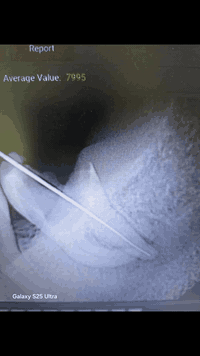

السلام عليكم الي محتاج قلع،طقم اسنان(جزئي متحرك )،حشوات تجميلية علماً ان العلاج مجاني وباشراف أطباء اختصاص ***********

قلع اسنان • طقم متحرك • مجاني كلية البيان

علاج مجاني • طقم اسنان جزئي • حشوات تجميلية

قلع أسنان • علاج مجاني • عيادات ذي قار